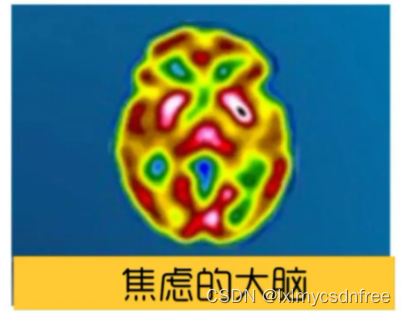

【脑结构的改变、认知变化】在焦虑的大脑中,杏仁核变得很大,回异常活跃;大脑中,除了杏仁核,还有额叶参与了焦虑的处理。杏仁核是情绪大脑的一部分。额叶就是认知大脑。只有当来自情绪大脑的信号压倒认知大脑并进入我们的意识时,我们才会感到焦虑。当杏仁核发出注意危险的警报时,前额叶皮层(PFC)应该像理性的顾问,启动分析处理信息,并帮你做出理性、合乎逻辑的反应。这个过程就像是踩刹车,抑制了被杏仁核夸大的信号。焦虑减弱了大脑部分联结,让理性反应受影响,焦虑会削弱杏仁核和前额叶皮层(PFC)之间的联系,这使杏仁核的刹车受损。焦虑也加强了大脑另一部分联结,使负面记忆留存,长期焦虑的大脑的海马体和杏仁核之间的连接性变得更强。其实当你焦虑时,压力会使大脑中处理长期和情境记忆的海马体收缩。海马体萎缩后,你的大脑保持记忆会有一定困难。然而麻烦的是,当你的海马体与杏仁核的联系比它与前额叶皮层的联系更紧密时,海马体就会保留与焦虑相关的记忆,可能记住的就是那些威胁、失败、危险,而不是存住快乐、成功和安.全的记忆。这会让你更加感到焦虑。